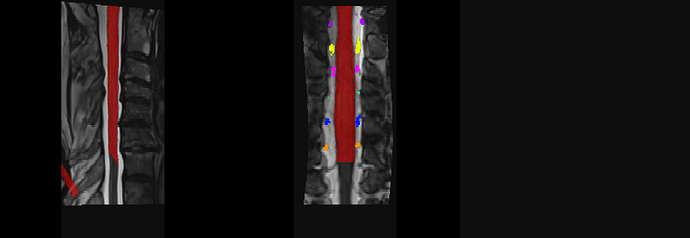

OK, I got it. Your syntax in this post was incorrect:

sct_apply_transfo -i t2_seg.nii.gz -d PAM50_t2.nii.gz -w warp_curve2straight.nii.gz warp_anat2template.nii.gz -o t2_seg_PAM50.nii.gz -x nn

You’re concatenating warp_curve2straight and warp_anat2template, but the latter transformation already includes warp_anat2template, so you’re essentially applying it twice. The correct syntax is:

sct_apply_transfo -i t2_seg.nii.gz -d $SCT_DIR/data/PAM50/template/PAM50_t2.nii.gz -w warp_anat2template.nii.gz -o t2_seg_PAM50.nii.gz -x nn

Which should then output:

Please follow the official example batch script provided in SCT’s website. Also go through the SCT course for more details on these processes.